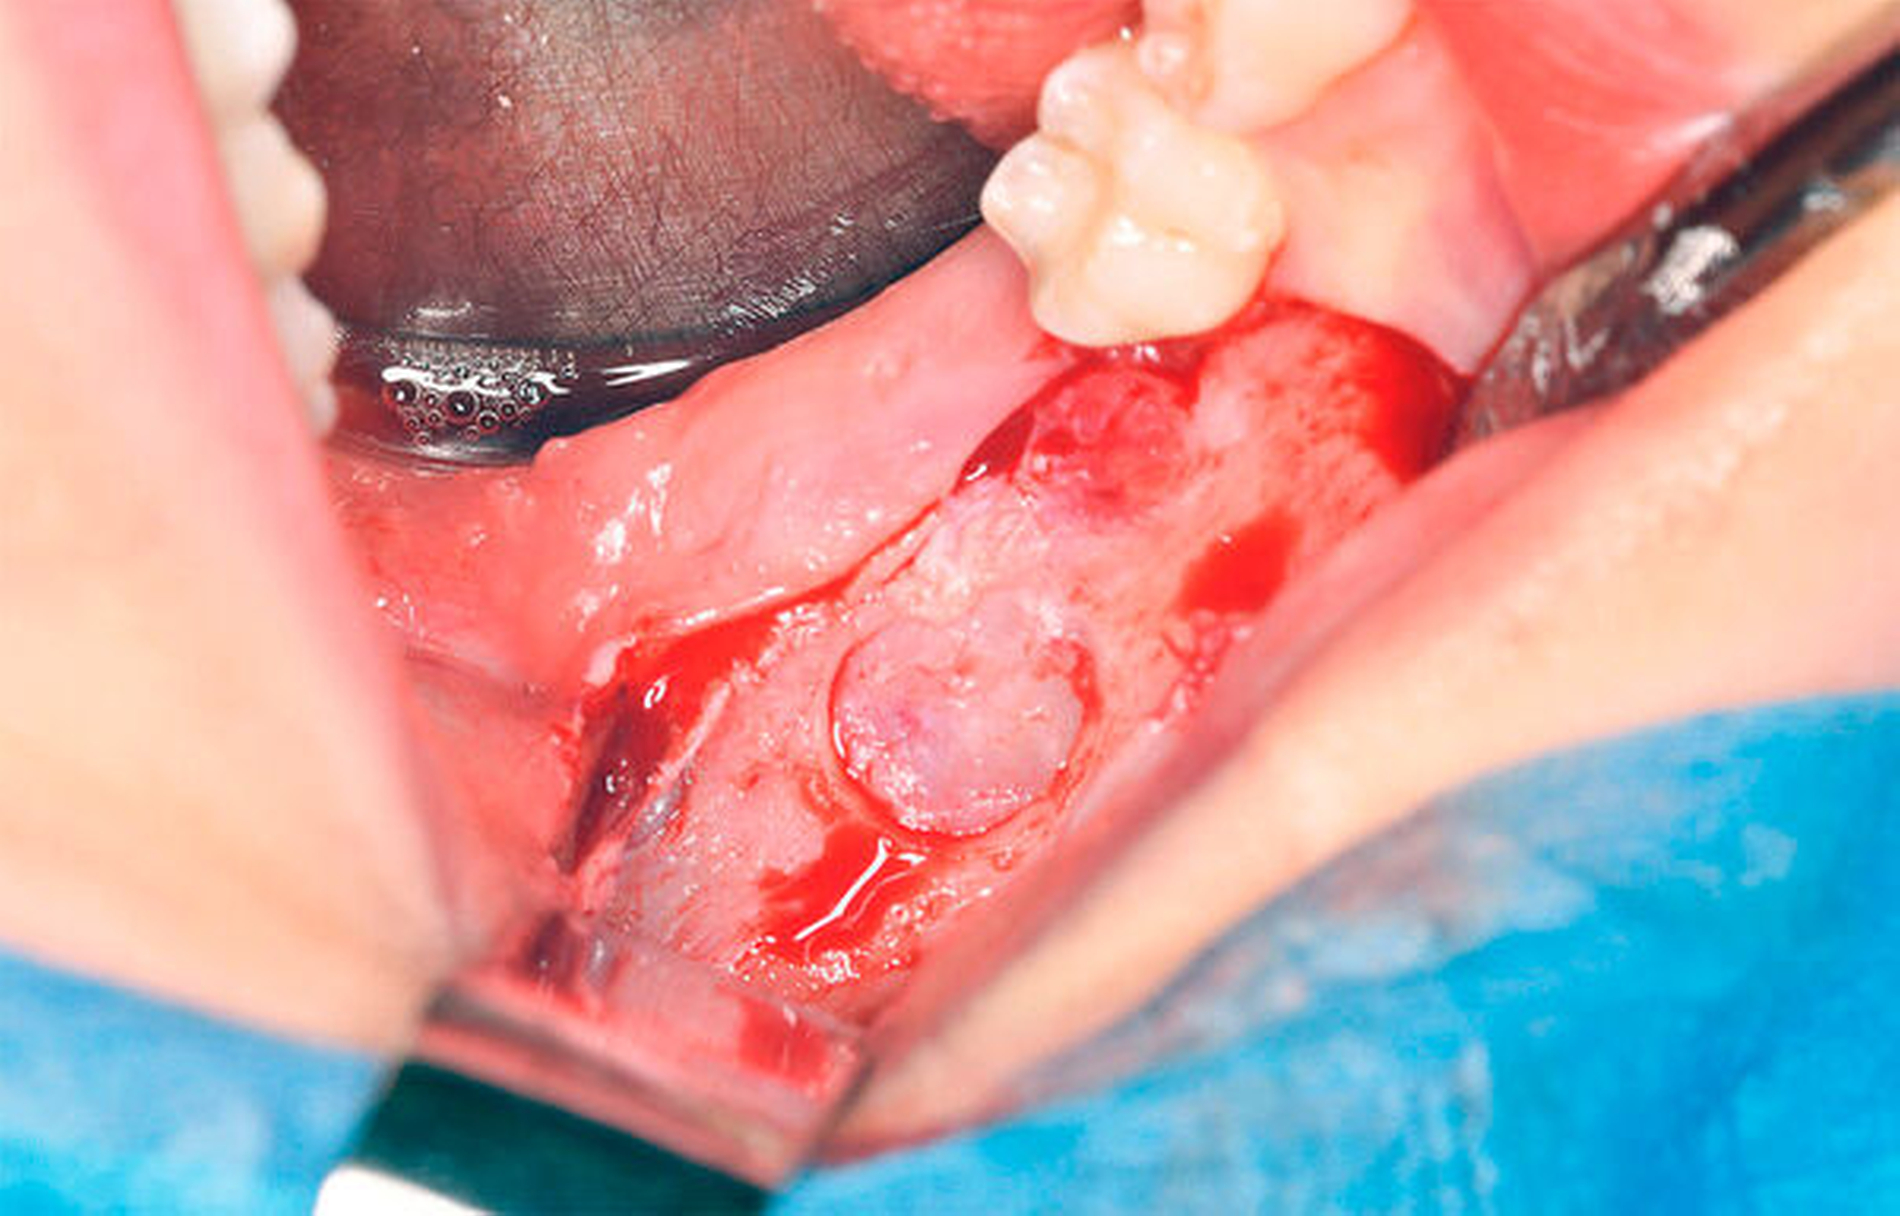

In Intubationsnarkose wurde vom aufsteigenden Ast kommend unter marginaler Schnittführung ein Mukoperiostlappen mit vestibulärer Entlastung am Zahn 45 präpariert. Unter vorsichtiger stumpfer Präparation erfolgte nun die Darstellung der Zyste (Abbildung 4) mit anschließender Eröffnung über einen osteoklastischen Zugang von vestibulär (Abbildung 5). Unter dem Schutz der Zähne 46 und 47 konnte der Zystenbalg mobilisiert und entfernt werden. Abschließend erfolgten der mehrschichtige Wundverschluss mit Fensterung nach vestibulär (Abbildung 6), eine intraoperative Alginatabformung zur Herstellung eines Obturators sowie die Einlage einer Tamponade.